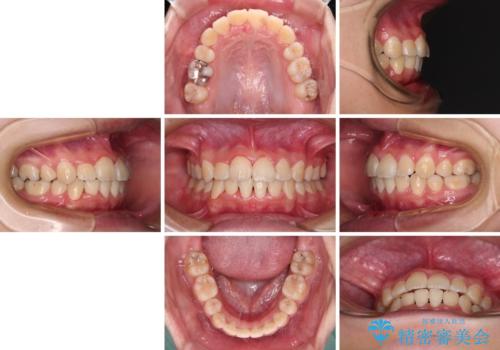

八重歯で正中が右にずれている ワイヤー装置での抜歯矯正で正中位置を改善

- 上下の八重歯と前歯のデコボコを気にして来院された患者様です。

右上の八重歯が特に著しく、上顎正中が右側にシフトしていました。

デコボコが強いため小臼歯4本を抜歯し、上顎正中を左側に移動させるために補助装置を使用して、ワイヤー装置にて矯正治療を行うこととしました。

正中位置の改善に時間がかかることが予想され、2年半を治療期間の目標としておりましたが、20歳と年齢が若いこともあり、2年2ヶ月で治療を終えることができました。